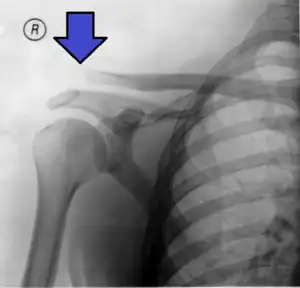

Type 3

Type 3 AC joint separation on plain X ray